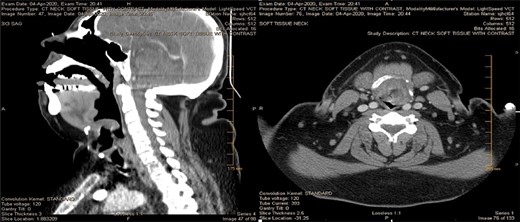

Computed tomography soft tissue neck with IV contrast (Fig. 2) revealed a nearly complete airway obstruction due to marked epiglottic enlargement and pre-epiglottic edema consistent with epiglottitis.

CT of the head/neck on the day of admission, sagittal and axial views. Imaging reveals a nearly complete airway obstruction with thumb sign (seen on the left) due to marked epiglottic enlargement and without tonsillar enlargement or abscesses.